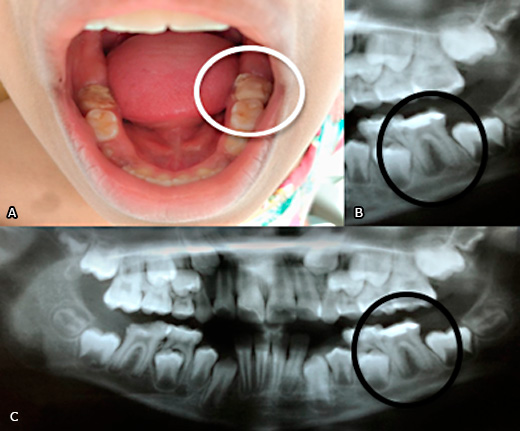

Realizou-se o exame físico intrabucal e pôde-se ratificar o péssimo estado de conservação da saúde bucal (índice de placa visível encontrava-se em 40%), como descrito no relatório de alta hospitalar chamando atenção os dentes 36 e 46 com extensa destruição coronária, comprometimento do espaço biológico periodontal e a presença de restaurações provisórias que ratificavam a historia da genitora quanto à tentativa de tratamentos conservadores (Fig. 2).

Fig. 2 – A: Condição intraoral da paciente, evidenciando restauração extensa dos molares inferiores 36 e 46. B e C: Radiografia panorâmica da paciente, indicando lesão associada a unidade 36.

Foi realizada a manobra semiotécnica digital de “ordenha” em assoalho de boca na região correspondente ao ápice das raízes do dente 36 por lingual onde se observou a drenagem de pequena quantidade de secreção (Fig. 1).Ao exame radiográfico panorâmico foi possível observar uma área radiolúcida entre as raízes do dente primeiro molar inferior direito (36) (Fig. 2).